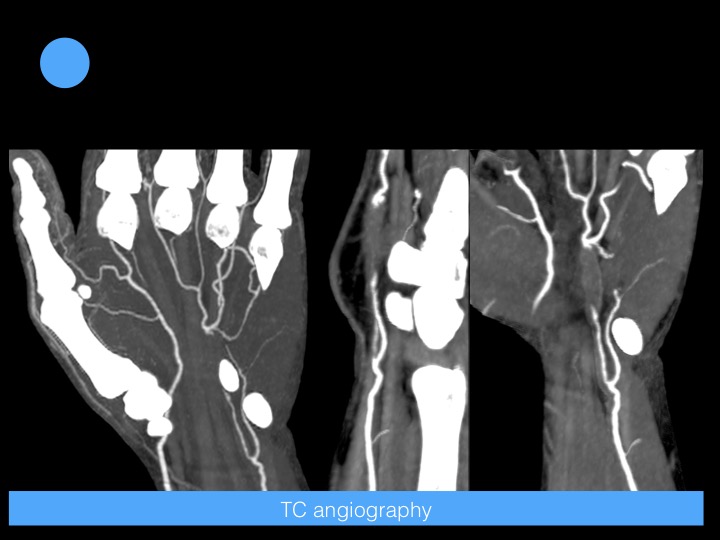

45-year-old man with unspecific pain and numbness in the hypothenar eminence

Hypothenar hammer syndrome is caused by blunt repetitive injury to the ulnar artery and superficial palmar arch from impact against the hamulus. Palmar arches and digital arteries also may be occluded.

Intimal hyperplasia is almost invariably present. Arterial wall damage may lead to aneurysm formation with or without vessel thrombosis and to microemboli formation and compression of the sensory branch of the ulnar nerve.

The diagnosis can be confirmed easily with Doppler ultrasound. However, CT angiography, or MR angiography is for precise vascular mapping. Reference article.

Hypothenar Hammer Syndrome